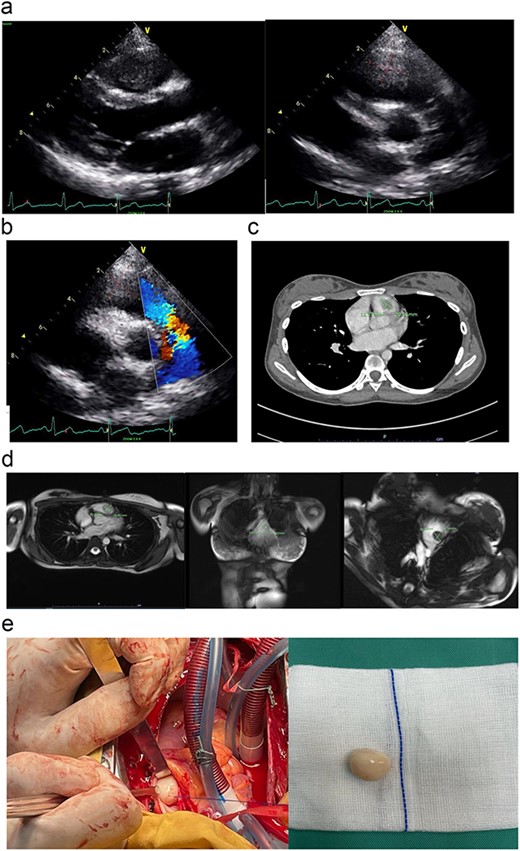

(a) The parasternal long-axis view of transthoracic ECHO showing a well-defined mass, measuring ~ (2.0 × 2.0 cm) at the right ventricle. (b) The transthoracic ECHO colour flow Doppler showed significant pulmonary valve stenosis with potential Right ventricular outflow tract obstruction caused by the intracardiac mass. (c) The axial cut of a contrast-enhanced computed tomography (CECT) thorax showed a well-defined mass measuring ~ (2 cm × 2 cm) inside the RV. (d) The cardiac magnetic resonance imaging (MRI) confirmed the diagnosis of right RV myxoma by showing a well-defined hypointense mass measuring ~ (1.7 × 2.0 cm). (e) The tumour was identified and excised via a median sternotomy, bicaval cannulation, cardiopulmonary bypass, hypothermia, and cardiac arrested via antegrade cold-blood cardioplegia. The tumour was excised via a pulmonary arteriotomy approach. The tumour is well-defined, firm in consistency, and smooth surface. The size is ~ (2 cm × 2 cm).

We performed the surgical removal of RV myxoma via a primary median sternotomy. A cardiopulmonary bypass is achieved using a central aortic and bicaval cannulation. The heart was vented via the right superior pulmonary vein and an aortic root vent. The patient was then cooled down to moderate hypothermia at 30°C. An aortic cross-clamp and an antegrade cold-blood cardioplegia were given to achieve diastolic arrest. We approach the mass by performing a horizontal arteriotomy over the main pulmonary artery, to inspect the pulmonary valve leaflet and the RVOT (Fig. 1e). After the complete removal of the myxoma (Fig. 1e), the pulmonary valve was tested again before the arteriotomy closure. The patient was then rewarmed to normothermia, and the cardiopulmonary bypass was terminated. The chest was then closed in the usual manner after a post-operative transoesophageal ECHO confirmed a patent pulmonary valve and no residual mass.